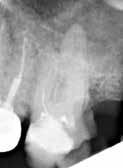

Fig. 8. Skematisk illustration af (A) en præmolar med 30º lingval kipning (18). Bor viser potentielt område for perforation (B) præmolar med 30º rotation (C) underkæbeincisiv med let/moderat kipning af roden, men overkontureret krone. Bor viser potentielt område for perforation. D. præmolar med distal kipning og molar med mesial kipning. Bor viser potentielt område for perforationer (18). E. Røntgenoptagelse af molar med let til moderat mesial kipning; bor viser perforationsområde.

F. Røntgenoptagelse af tand med mesialt placeret oplukningskavitet og fremmedlegeme i alveoleknoglen som følge af perforation.

Fig. 8. Schematic illustration of (A) a premolar with 30º lingual tilt (18). Bur showing potential area of perforation (B) premolar with a 30º rotation (C) lower incisor with a mild/moderate tilt in the root but an over-contoured crown. Bur showing potential area of perforation. D. premolar with distal tilt and molar with mesial tilt. Bur showing potential area of perforations (18). E. Radiograph showing a molar with a mild to moderate mesial tilt with bur showing area of perforation. F. Radiograph of tooth with mesially placed access cavity preparation and foreign material lodged in the alveolar bone due to perforation.

En tandlæge i Kategori A har ikke erhvervet tilstrækkelige færdigheder til at kunne modificere oplukningskavitetens udformning i en tand, der er kippet eller roteret. For at undgå unødvendige uheld som perforation i forbindelse med oplukningen (Fig. 8A-F) bør sådanne tænder kun behandles af tandlæger, der mindst er i Kategori B.